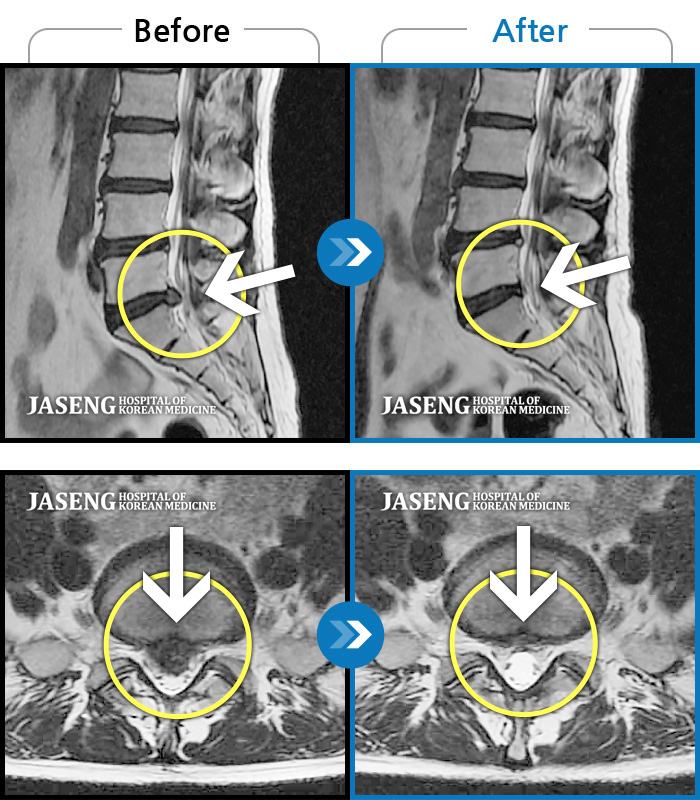

허리디스크

안산 · 김민수 원장

허리가 아프고 두 다리가 저려서 조금만 걸어도 주저 앉아야 했습니다.

촬영시기

2018.12.20 ~ 2023.02.21

2023.02.24